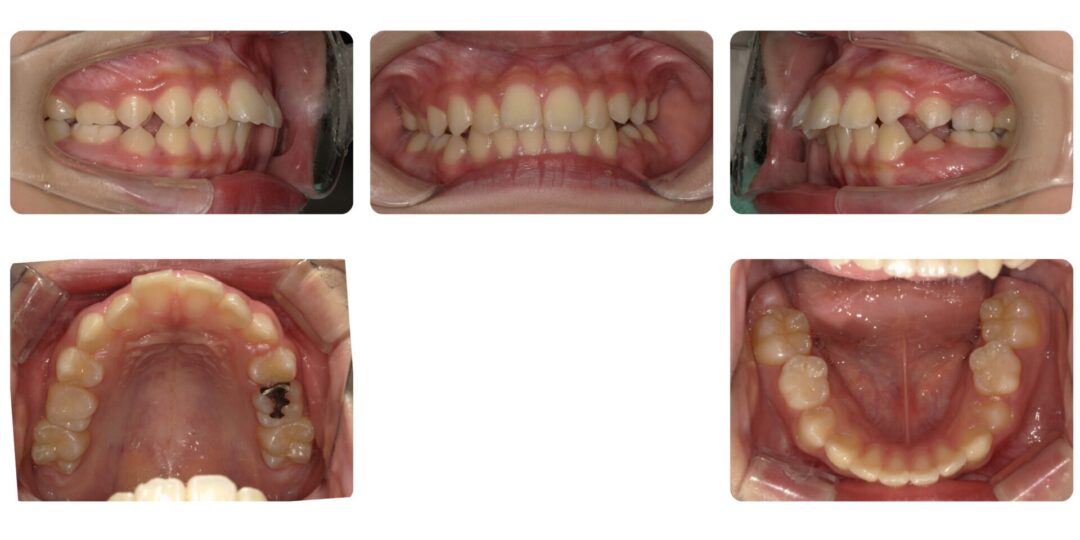

骨格性上顎前突|初診時10歳

矯正治療前

治療内容

第一期治療 拡大床ネジ付きバイオネーターによる歯列矯正

治療期間

1年4ヶ月

治療費用

自由診療 基本料金¥330,000 処置料¥3,300